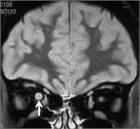

1. MRIのSTIR法は、視神経炎の病態把握に有用で推奨される(推奨度1)

1. 視神経炎の活動性炎症の有無はMRIのT1強調画像脂肪抑制造影で判断する(推奨度1)